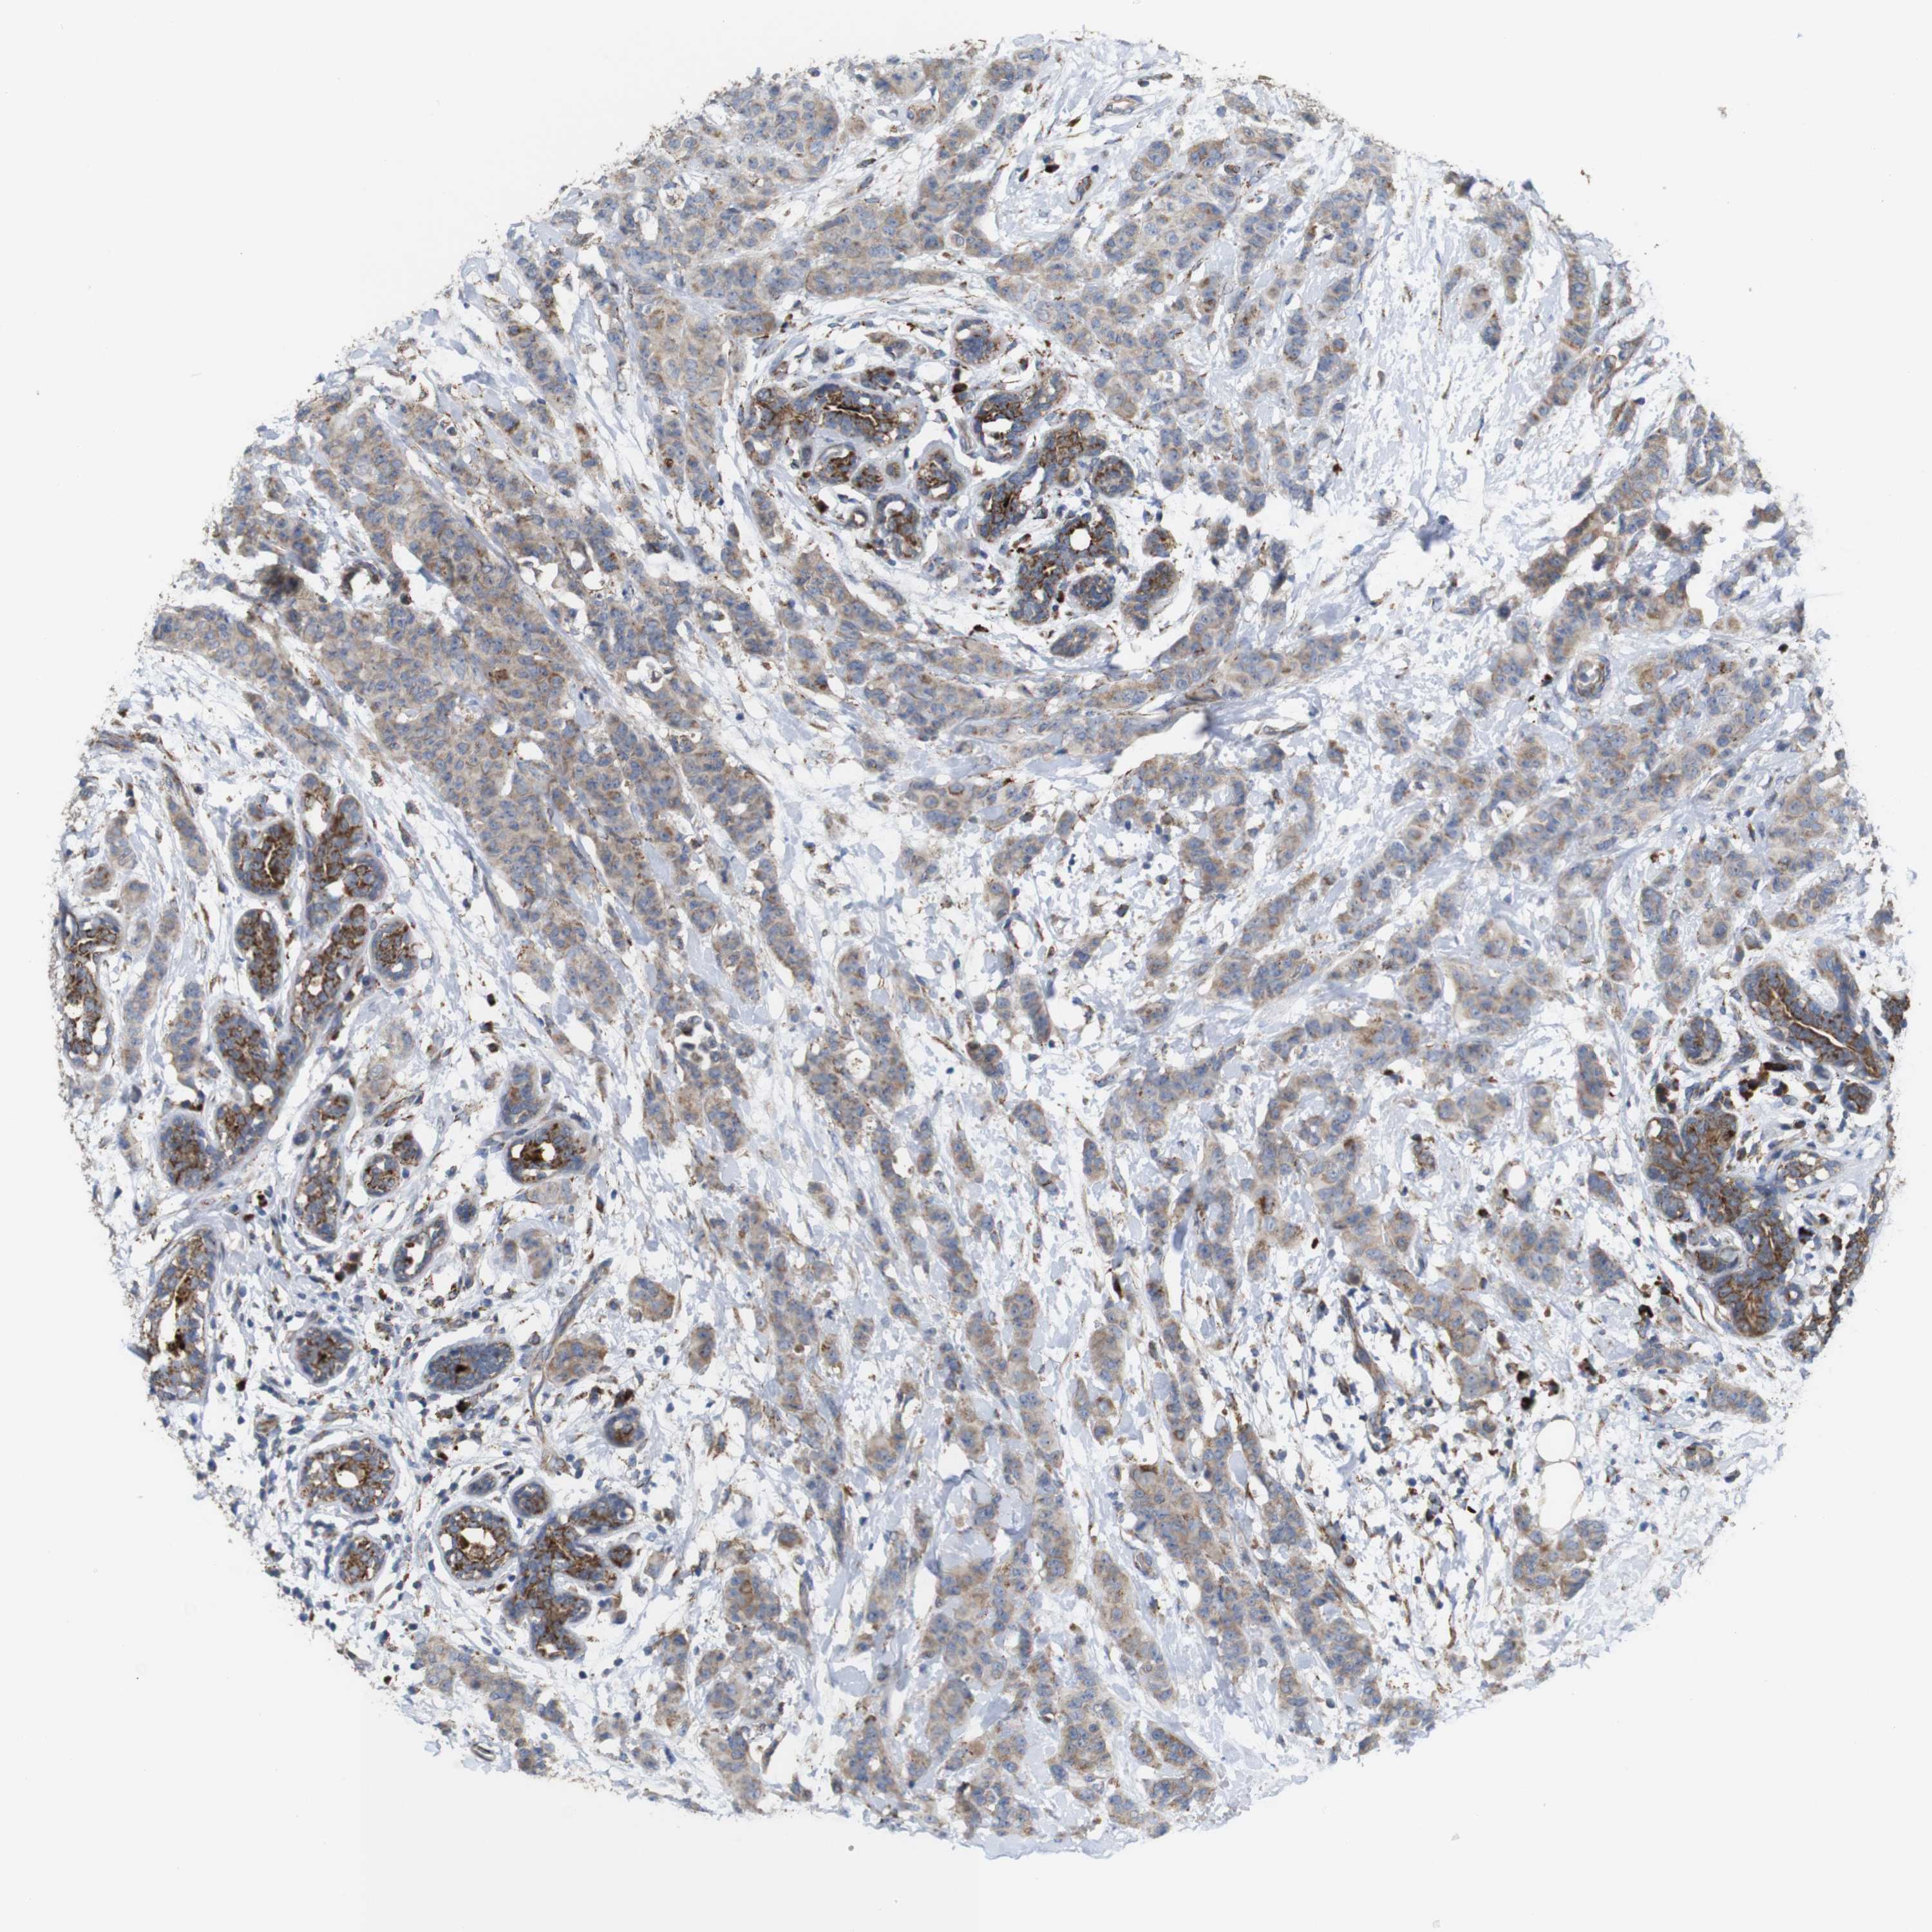

CANCER BREAST CANCER Show tissue menu

BRCA TCGA BRCA VALIDATION PROTEIN EXPRESSION